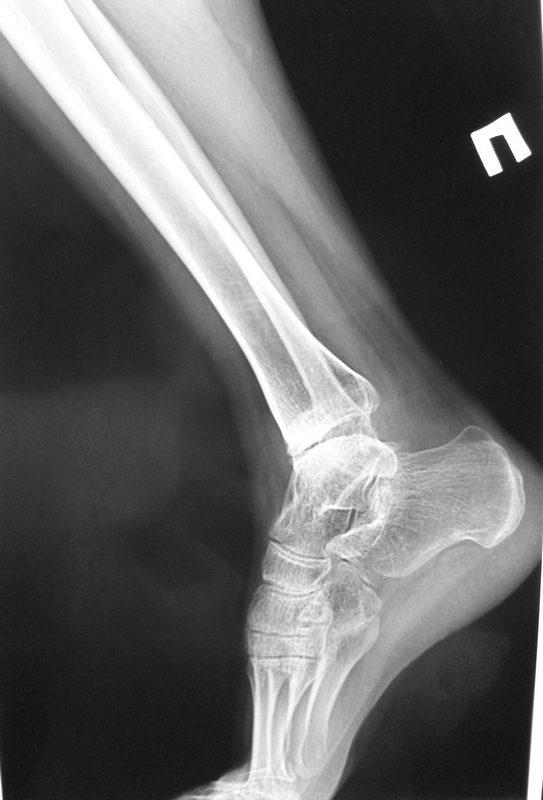

1.У пациентки перелом внутренней лодыжки сросся. Это видно из рентгенограмм. Болей нет.

> У пациентки перелом внутренней лодыжки сросся. Это видно из рентгенограмм. Болей нет.

Я вижу суперпозицию смещенной кпереди внутренней лодыжки и кортикальные замыкательные пластинки на центральном и периферическом отломках. Может сращение где-то на ограниченном участке и есть, но по имеющейся информации говорить об этом трудно. На данные КТ 2012г.!!! расчитывать не приходится.

> Эквинусная установка за счет переднего отдела.

наверное я слепой...

Наверное прежде чем планировать что-то хирургическое нужно получить правильные снимки. Здесь передне-задняя проекция видимо с наружной ротацией стопы. Хотелось бы глянуть на синдесмозную проекцию.

Меня больше всего смущает подвывих стопы кпереди. Возможно это связано с нерепонированной внутренней лодыжкой (ощущение, что она смещена кпереди).

Согласен. Типичная картина при плохо отрепонированной внутренней лодыжки.